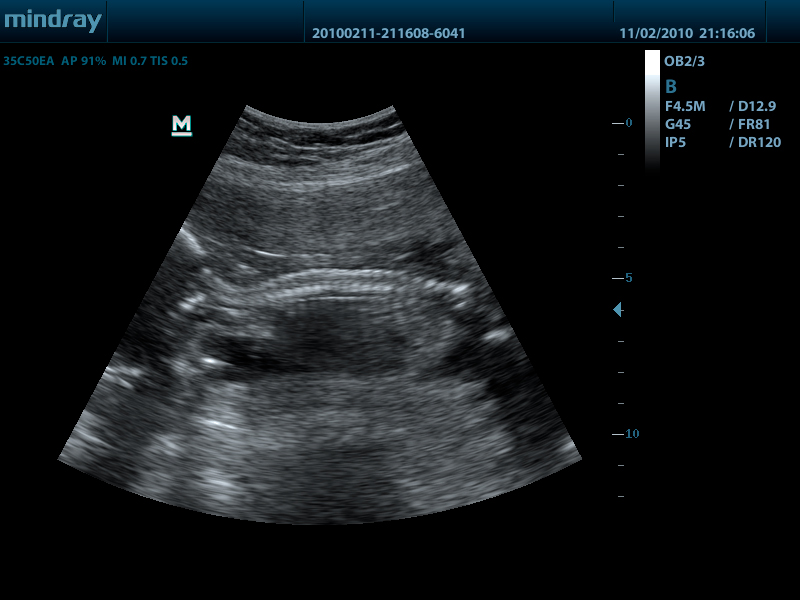

Mindray DP-50 – портативная цифровая ультразвуковая система с ЖК монитором 15 дюймов (1024Х768)

- iClear технология подавления помех и получения четких ультразвуковых изображений высокого разрешения

DP-50 – портативный УЗИ сканер разработан на базе новой платформы X-treme engine, используемой в хорошо зарекомендовавших себя цветных сканерах с доплером моделей DC-3, DC-7, DC-6. Эта платформа открывает возможности для расширений до уровня цветных сканеров и совместимости с широким диапазоном периферийного оборудования. X-treme означает интеллект, высокую скорость обработки данных, многоуровневую передачу сигналов, а также возможность оптимизации изображения и модульного расширения.

Качество изображения:

- iBeam: функция улучшения разрешающей способности изображения

- iClear: функция подавления шумов на изображении для улучшения детализации и контрастности изображения

Конвексный датчик 35C50EA (2.0/3.5/4.5/5.0/Н5.0/Н6.0) R50